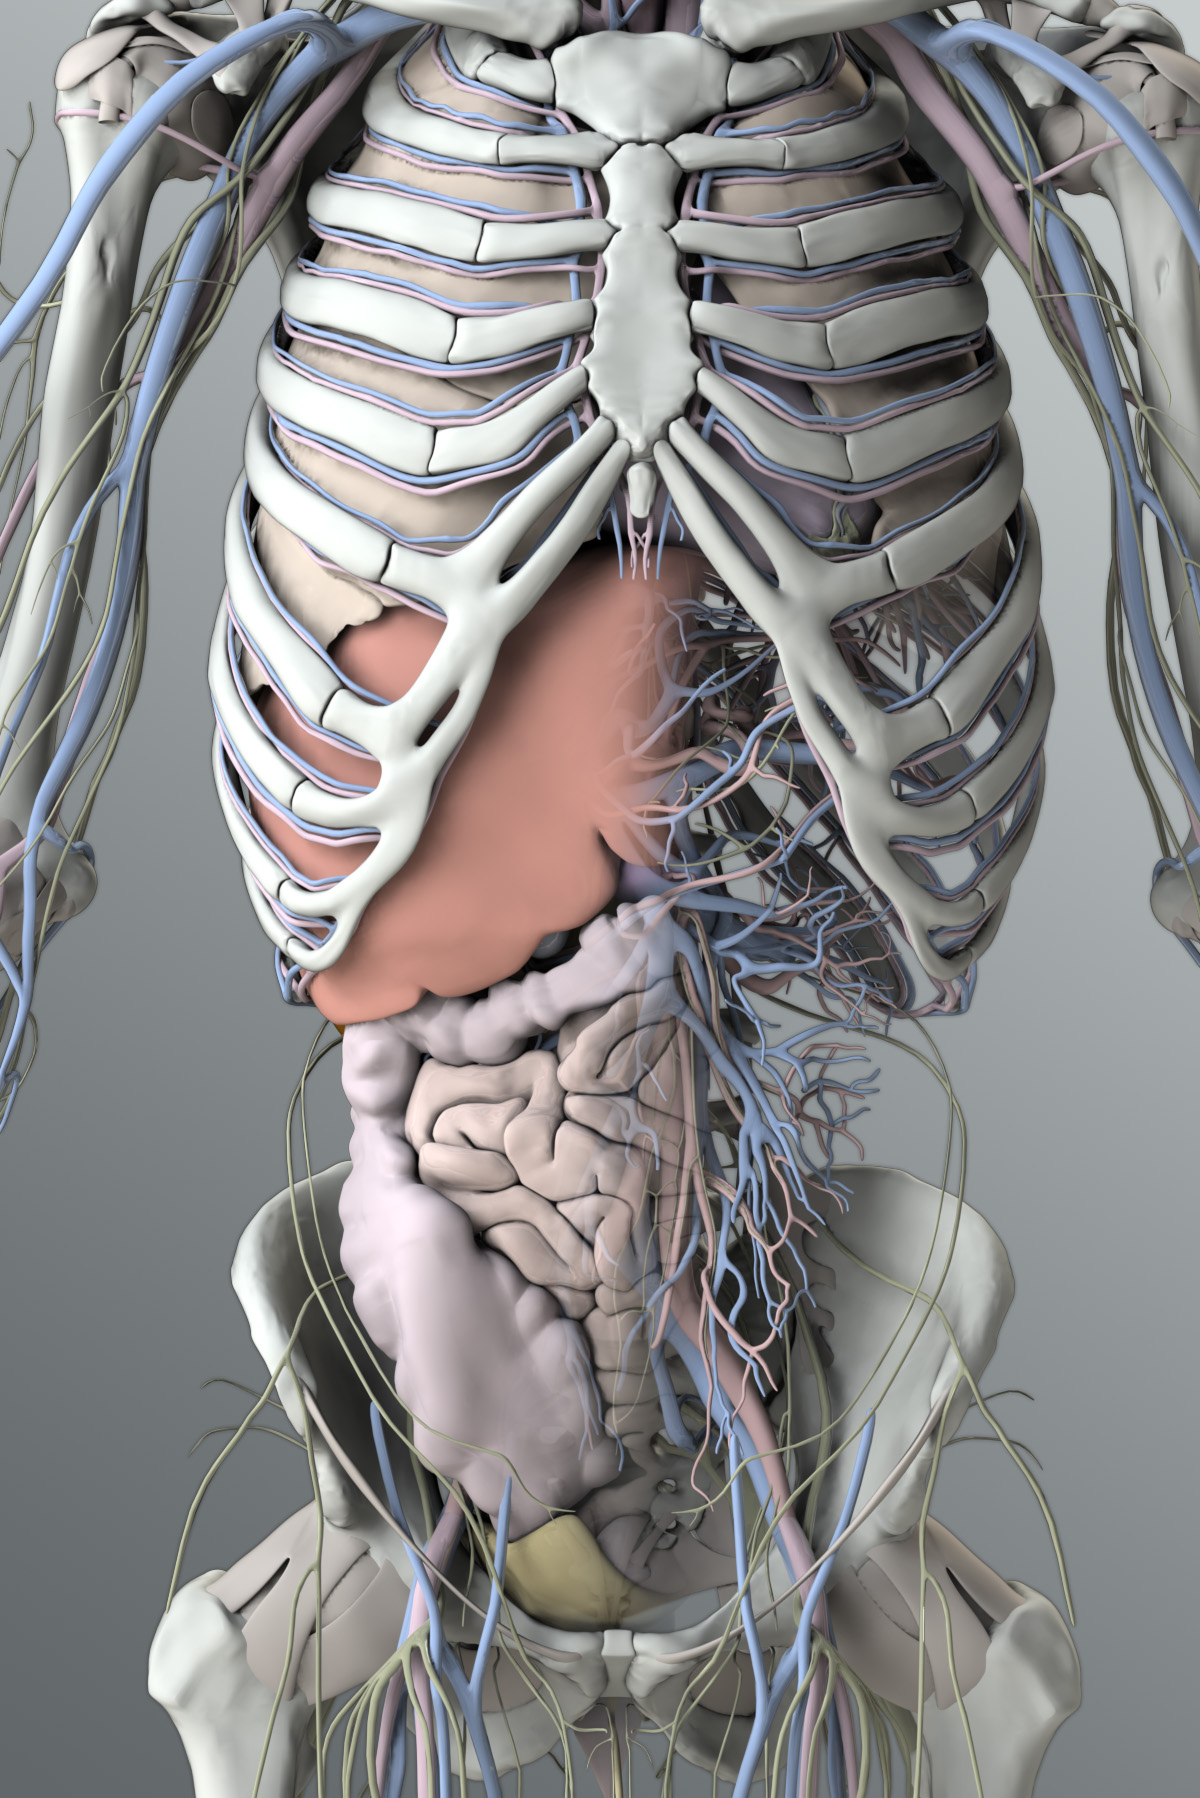

Human Male Organ Locations

Human Male Organ Locations

Transparent Body Model Showing Male Anatomy And Internal Organs

Male Organ Location Diagram

Male Organ Location Diagram